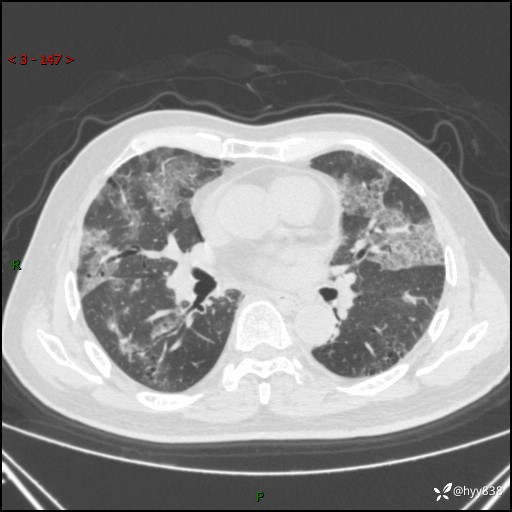

患者性别:男

患者年龄:64岁

简要病史:肝内胆管癌综合治疗后2周余,咳嗽、发热,咳白色泡沫痰。

辅助检查:CT

临床诊断:感染?

讨论:病变性质?